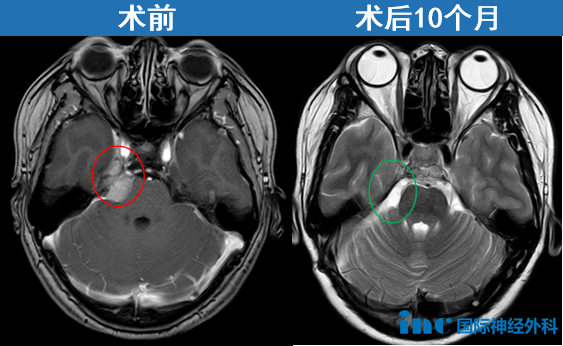

偶然发现脑膜瘤在INC国际教授手术交流中很常见,他们会如何决策——36岁患者小宛在一次体检中偶然发现脑膜瘤,肿瘤一直未显现症状。面对这个"静止性"病变,小宛没有过多犹豫就做出决定。在北京天坛医院,INC福教授为她成功手术——"我在ICU停留4个多小时就转出,术后第2天下床活动,第9天出院。"

点击阅读:天坛医院手术纪实 | 4.5cm脑膜瘤紧压脑干成功手术,勇敢辣妈的彪悍人生!